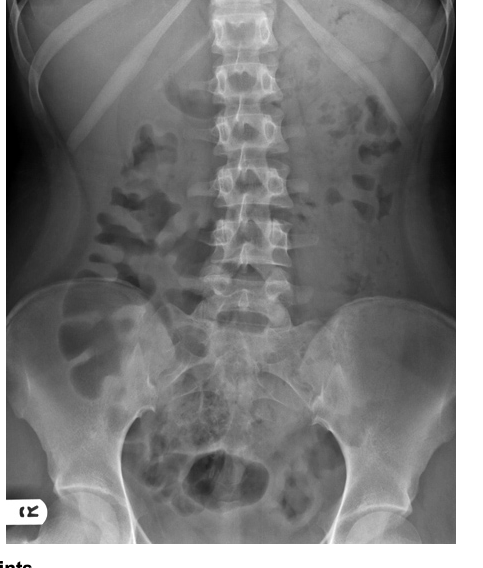

Patient with severe abdominal pain. What is the cause of pain demonstrated on this abdominal X-ray?

Caecal volvulus

Normal appearances

Pneumoperitoneum

Small bowel obstruction

Toxic megacolon

A